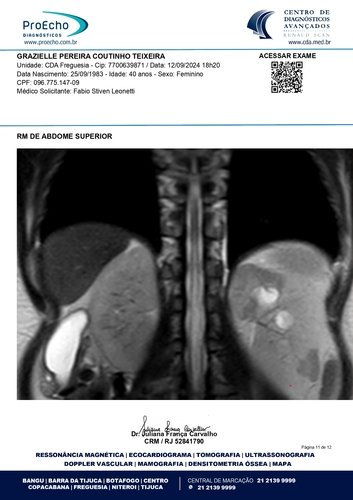

Olá, meu nome é Grazielle, tenho 41 anos e estou enfrentando a batalha mais difícil da minha vida. Fui diagnosticada com quatro miomas, sendo que o maior deles mede 30 x 20 x 28 cm e está comprimindo meus órgãos internos, além de endometriose, um cisto no ovário direito, mucocele de apêndice e um nódulo no intestino. Minha barriga está tão inchada que parece a de uma mulher grávida de 9 meses. Mas, apesar da aparência, o que mais preocupa os médicos é o apêndice inflamado. Se ele estourar, pode causar uma infecção generalizada e me levar a óbito. O tempo é curto: os médicos recomendaram que eu faça a cirurgia no máximo em três meses.

Abaixo, você encontrará os laudos médicos e imagens dos exames que comprovam o meu diagnóstico, bem como o orçamento detalhado da cirurgia. Se tiver alguma dúvida, estarei à disposição para fornecer mais informações.

Ressonância magnética: https://drive.google.com/file/d/1oSvors6sJRCRTZHVSZs9YeKzpw54SFw5/view?usp=sharing